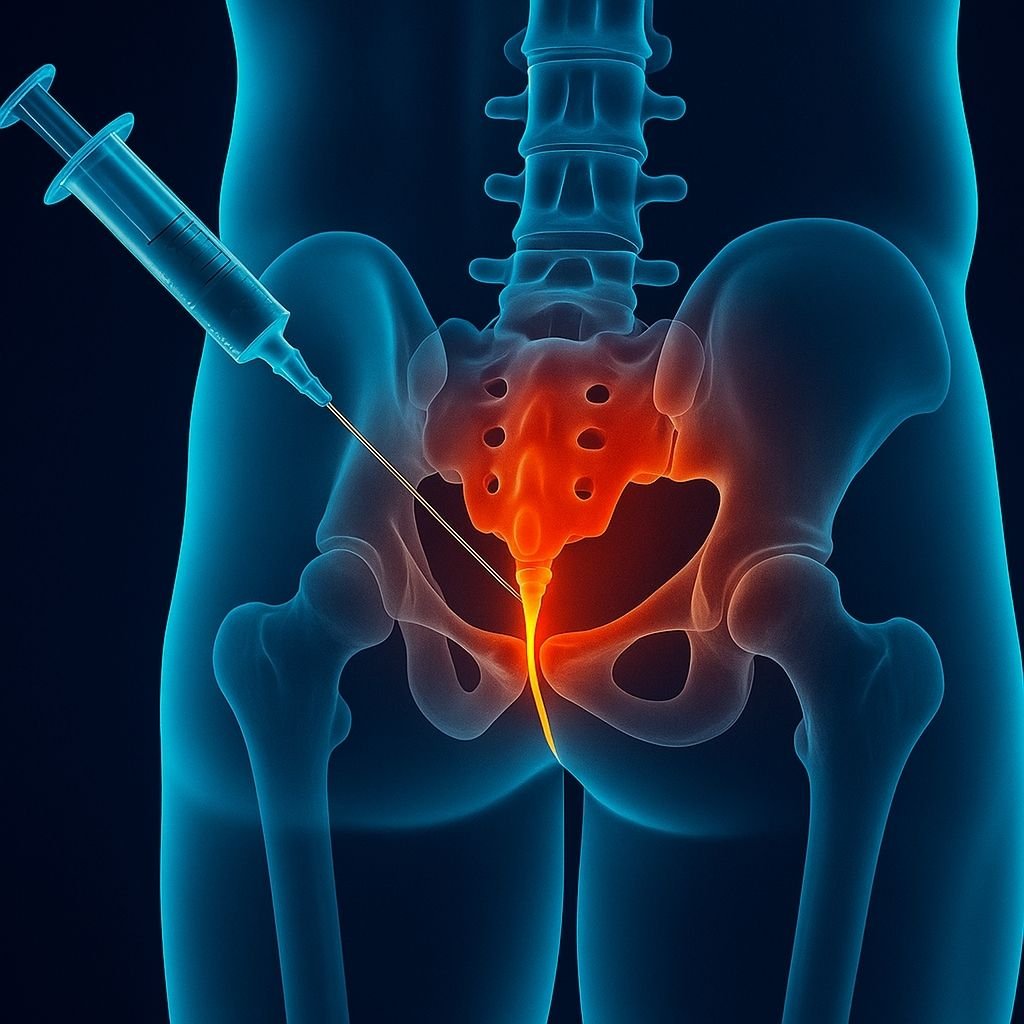

Omurga kanalında çıkan sinir kökleri, bel fıtığı veya dar kanal gibi nedenlerle bası altında kalabilir. Bu durum belden bacağa yayılan şiddetli ağrılara yol açar. Transforaminal epidural steroid enjeksiyonu, sinir köklerinin çıktığı foramen adı verilen bölgeye steroid ve lokal anestezik ilaç enjekte edilmesi işlemidir. Bu sayede sinir çevresindeki iltihap azalır, ödem giderilir ve ağrı sinyalleri bloke edilir.

Hasta yüzüstü yatırılır.

Floroskopi (X-ray) cihazı ile ilgili omurga seviyesi görüntülenir.

İnce bir iğne, sinir kökünün çıktığı foramene yönlendirilir.

İğnenin doğru yerde olduğu kontrast madde ile teyit edilir.

Steroid ve lokal anestezik ilaç, sinirin etrafına enjekte edilir.

İşlem ortalama 20 dakika sürer, hasta kısa sürede ayağa kalkabilir.